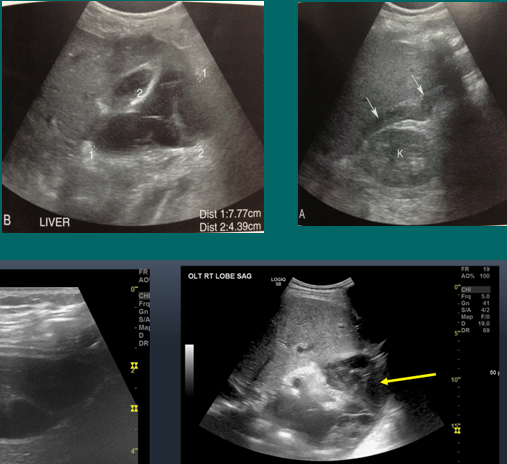

HA thrombosis

HAT

hepatic artery stenosis (HAS)

portal vein thrombosis (PVT)

portal vein stenosis (PVS)